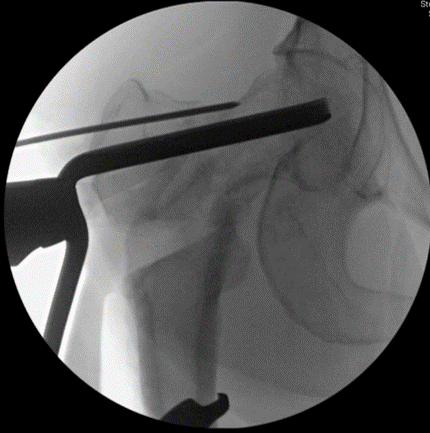

The plate is inserted. Notice the wire above the plate- this is to ensure no rotatory #malalignment is created after the #osteotomy

Post-op xrays after the procedure. The overall alignment of the hip has been restored. The patient is given crutches and toe-touch restrictions for 6 weeks #postop #traumacase #orthopaedics